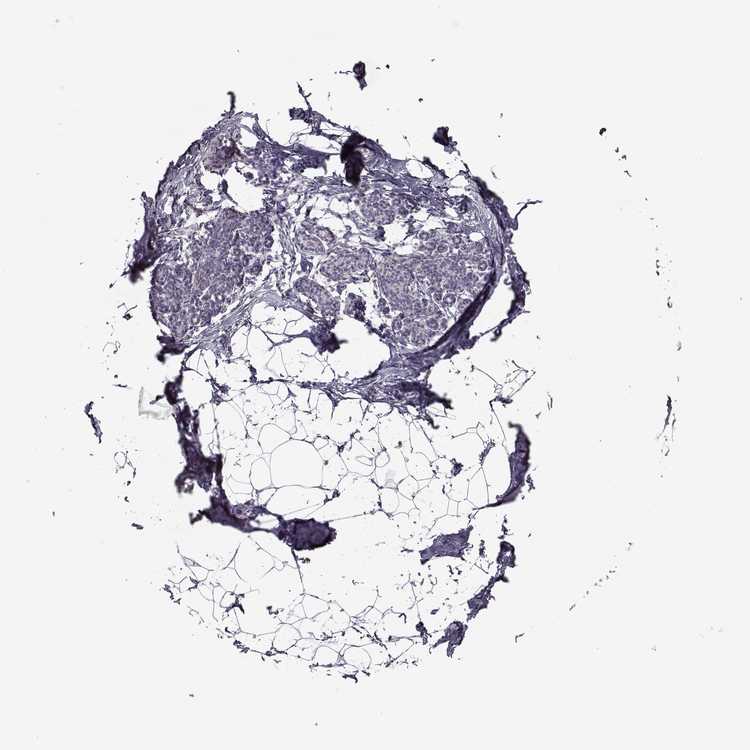

BREAST - Antibody stainingi

Antibody staining in the annotated cell types in the current human tissue is reported as not detected, low, medium, or high, based on conventional immunohistochemistry profiling in selected tissues. This score is based on the combination of the staining intensity and fraction of stained cells.

Each image is clickable and will lead to virtual microscopy that enables deeper exploration of all samples and also displays staining intensity scores, fraction scores and subcellular localization as well as patient and tissue information for each sample.

Antibody HPA005459Antibody CAB010877

Adipocytes Not detectedNot detected

Glandular cells Not detectedNot detected

Myoepithelial cells Not detectedNot detected